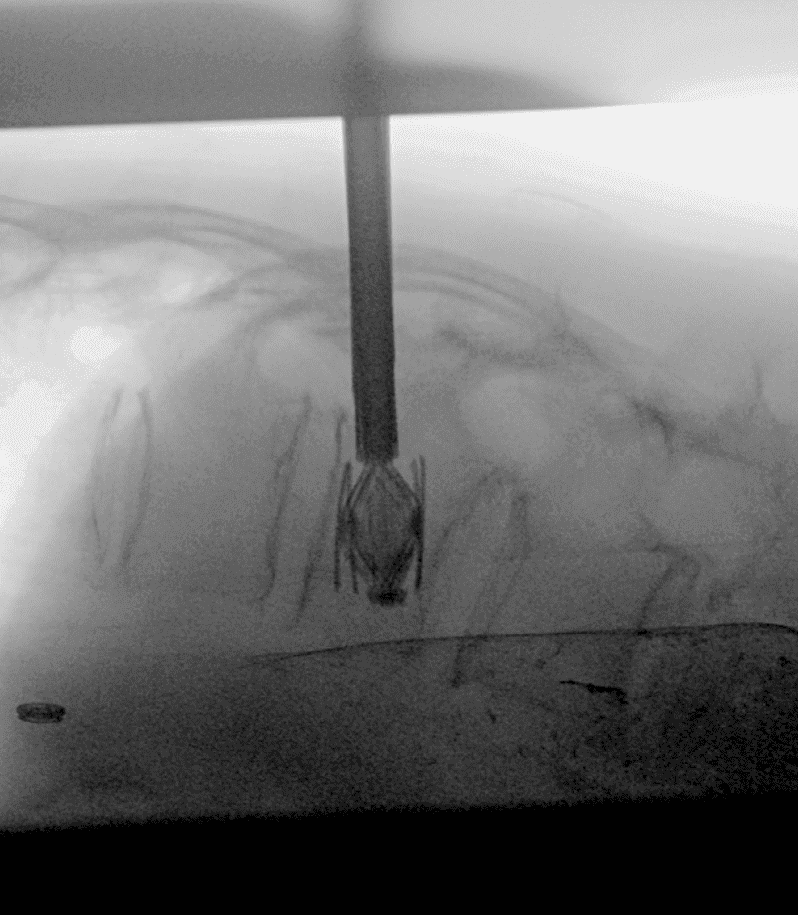

CT

Technique de traitement des fractures vertébrales ostéoporotiques